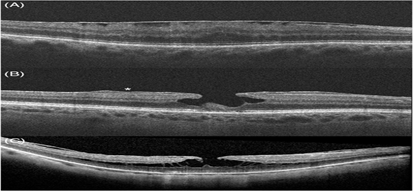

Hình ảnh trên OCT của màng trước võng mạc và các khái niệm có liên quan: A- màng trước võng mạc, B- lỗ lớp hoàng điểm cùng với tăng sinh trước võng mạc (dấu sao), C- tách lớp VM

OCT đã trở thành một xét nghiệm phụ hữu ích nhất trong chẩn đoán ERM và nhạy hơn so với xét nghiệm lâm sàng đơn thuần. Nó có ưu điểm hơn so với các hệ thống phân loại dựa trên mô tả vì không chỉ cho phép mô tả định tính chính xác mà còn cho phép phân tích định lượng và mối tương quan với tiên lượng hình ảnh.

Sự thay đổi từ phương pháp soi sinh học bằng đèn khe truyền thống sang phương pháp chụp ảnh cắt lớp võng mạc thế hệ SD-OCT đã dẫn đến nhu cầu sửa đổi các định nghĩa lỗi thời về các bệnh võng mạc vốn có thể khó phân biệt với nhau. Giờ đây các bác sĩ có thê phân định chính xác các tổn thương sau đây với nhau:

Sự nhất trí về các định nghĩa cho các tình trạng võng mạc này đã làm giảm bất đồng trong chẩn đoán của các bác sĩ và thúc đẩy áp dụng thêm nhiều công nghệ mới để điều trị ERM.